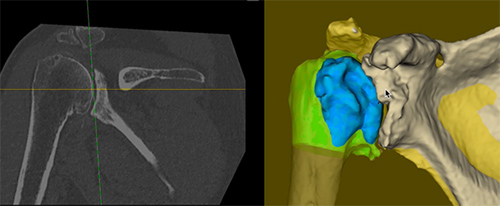

Mako SmartRoboticsâ„¢ combines 3D imaging, robotic arm assistance, and advanced surgical planning to help your surgeon perform shoulder replacement with greater accuracy than traditional methods. Before surgery, a CT scan creates a personalized 3D model of your shoulder. This allows Dr. Hill to design a surgical plan tailored to your anatomy.

During surgery, the Mako system provides real-time guidance and haptic technology to help ensure implant components are placed exactly as planned, preserving bone and protecting surrounding tissue.